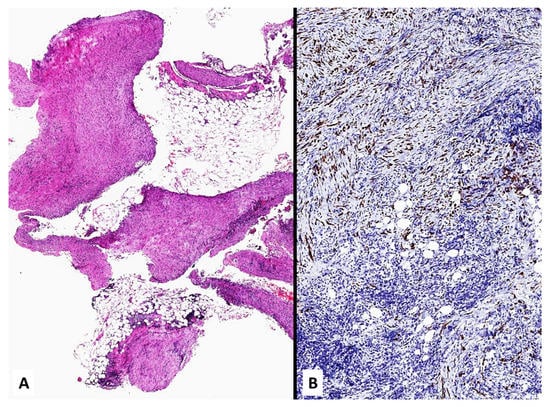

4. Unusual Morphologic and Immunohistochemical Features

- Cigognetti, M.; Lonardi, S.; Fisogni, S.; Balzarini, P.; Pellegrini, V.; Tironi, A.; Bercich, L.; Bugatti, M.; De Rossi, G.; Murer, B.; et al. BAP1 (BRCA1-associated protein 1) is a highly specific marker for differentiating mesothelioma from reactive mesothelial proliferations. Mod. Pathol. 2015, 28, 1043–1057. [Google Scholar] [CrossRef] [PubMed]

- Hida, T.; Hamasaki, M.; Matsumoto, S.; Sato, A.; Tsujimura, T.; Kawahara, K.; Iwasaki, A.; Okamoto, T.; Oda, Y.; Honda, H.; et al. Immunohistochemical detection of MTAP and BAP1 protein loss for mesothelioma diagnosis: Comparison with 9p21 FISH and BAP1 immunohistochemistry. Lung Cancer 2017, 104, 98–105. [Google Scholar] [CrossRef]

- Chapel, D.B.; Schulte, J.J.; Berg, K.; Churg, A.; Dacic, S.; Fitzpatrick, C.; Galateau-Salle, F.; Hiroshima, K.; Krausz, T.; Le Stang, N.; et al. MTAP immunohistochemistry is an accurate and reproducible surrogate for CDKN2A fluorescence in situ hybridization in diagnosis of malignant pleural mesothelioma. Mod. Pathol. 2019, 33, 245–254. [Google Scholar] [CrossRef]